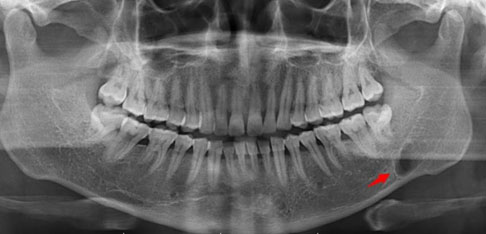

Case Report: A 42-year-old healthy man without underlying diseases or any teeth troubles suffered from severe pain in the gingival of the right mandibular bone for three weeks. The intraoral inspection revealed a well-defined elastic hard mass with a size less than 10 mm on the medial side of the right mandibular gingiva. The histopathological examination proved that the bacterial druse with radial structure invaded the bone margin widely and proliferated in some places of the bone. After removing the mass and scraping off the around bone, followed by two month-oral use of Amoxicillin (AMPC:1500 mg/day), his complaints and the gingival tissue have been entirely resolved.

Conclusion: The morphological features of the growth of actinomyces in the bone margin by the limited lesion of actinomycosis at the gingiva have not ever been reported. Even localized actinomycosis at gingiva should be adequately treated.